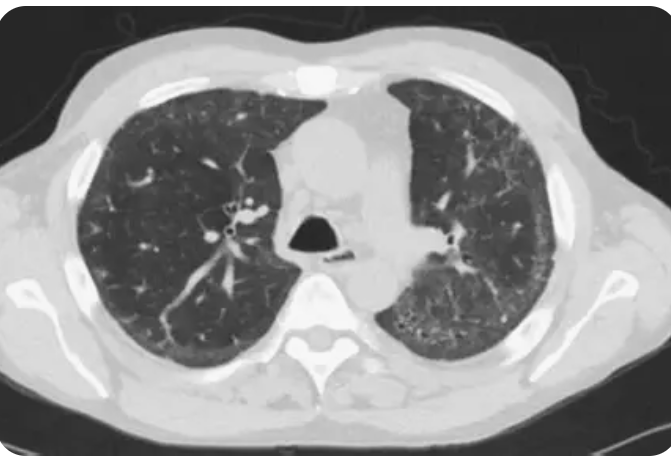

25

HRCT pattern systemic sclerosis

Usually NSIP Can be UIP